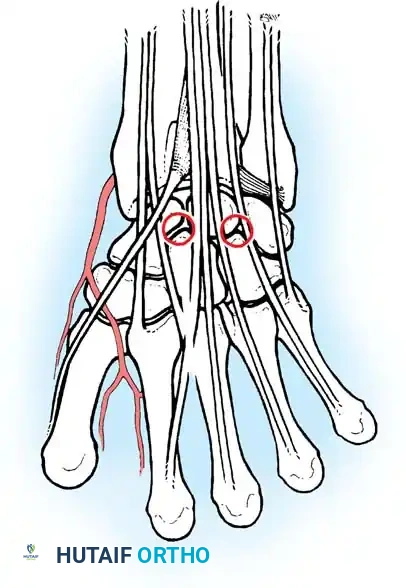

Wrist arthroscopy portals are anatomically defined by their relationship to the six dorsal extensor compartments. Precise portal placement is critical to avoid injury to cutaneous nerves, extensor tendons, and articular cartilage.

- 6U Portal: Located immediately ulnar to the ECU tendon. Risk: The dorsal sensory branch of the ulnar nerve (DSBUN).

Volar Portals

While less commonly used, volar portals (volar radial and volar ulnar) are gaining traction for specific indications, such as evaluating dorsal capsular avulsions or repairing volar TFCC tears. These require meticulous blunt dissection due to the proximity of major neurovascular bundles (radial artery, median nerve, ulnar artery/nerve).

- Portal and Insertion Complications:

- Nerve Injury: The SBRN is highly vulnerable at the 1-2 portal, and the DSBUN is at risk at the 6U portal. Strict adherence to blunt subcutaneous dissection is mandatory.